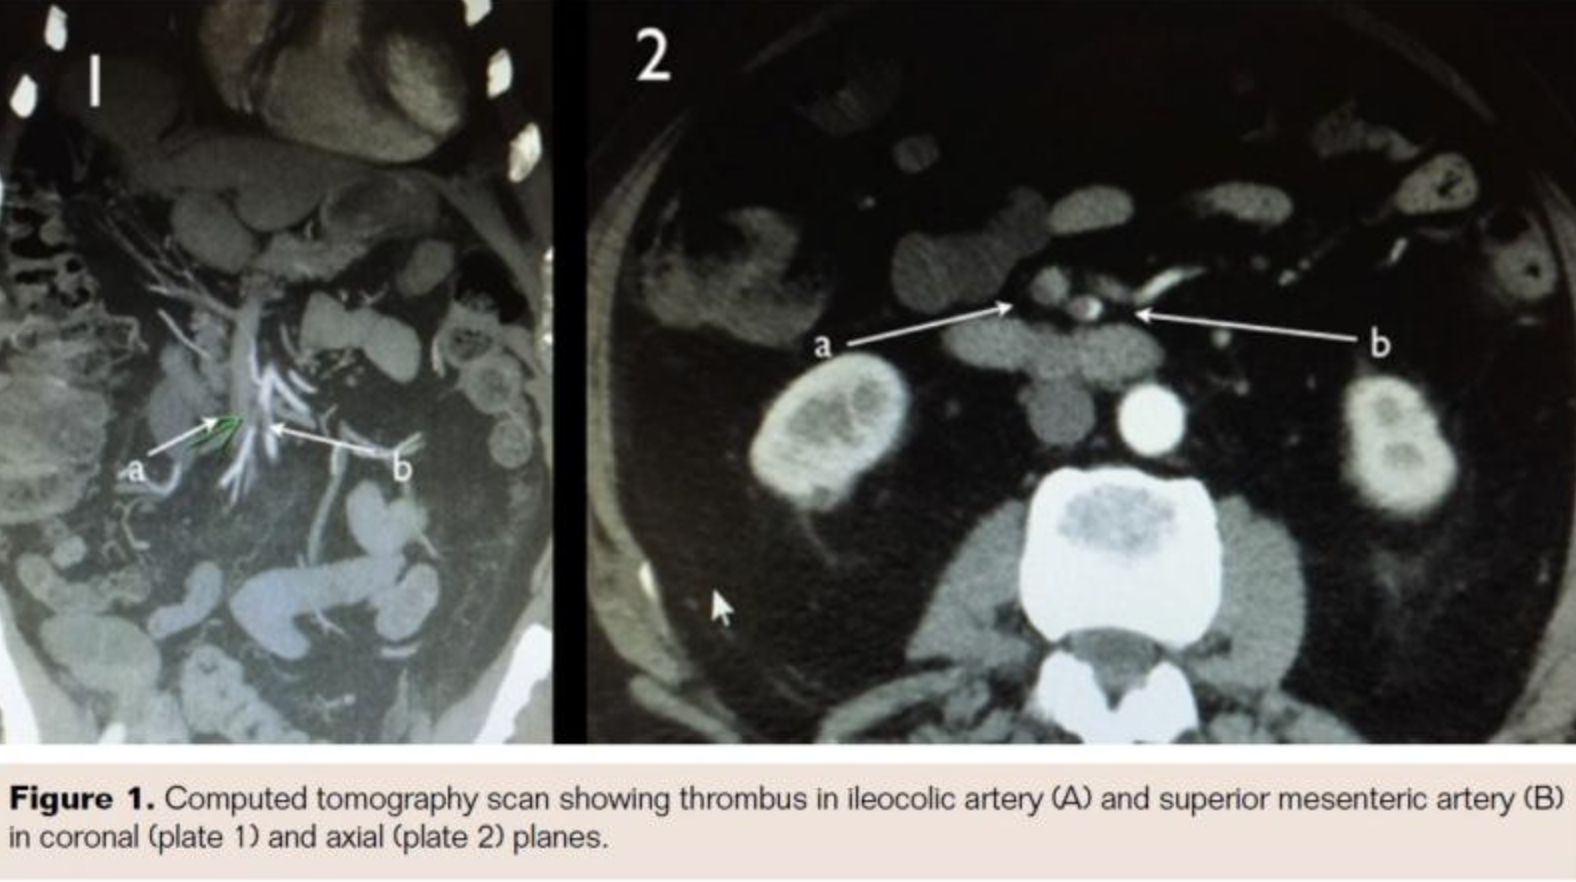

The patient was taken for urgent angiography due to rapid rise in biomarkers reflecting early bowel necrosis. Right femoral artery access was obtained and cannulated with a 6 Fr sheath. A 4 Fr internal mammary catheter was used to cannulate the superior mesenteric artery (SMA). The catheter was advanced into the proximal segment of the vessel over a Glidewire (Terumo). Angiography via the internal mammary catheter confirmed the CT angiographic findings. This catheter was exchanged for a 6 Fr, 55 cm Ansel guiding sheath (Cook Medical). Activated clotting time was 177 seconds, and heparin 3,000 U bolus was administered intravenously. A 0.014˝ wire was advanced through the occluded distal SMA and thrombectomy was done using an Angiojet XVG thrombectomy catheter with complete resolution of the thrombus (Figure 2). The wire was then advanced into the ileocolic artery, which was treated with a similar technique (Figure 3). The proximal segment of the ileocolic artery showed thrombus resolution but a large branch of this vessel was still occluded. Thrombectomy in this branch did not re-establish flow in the vessel, and the angiographic appearance was consistent with diffuse spasm. A 135 cm Cragg-Mcnamara Valved Infusion Catheter (Medtronic) with 10 cm infusion length was then advanced into this branch (Figure 4) and intra-arterial papaverine was administered via this catheter at 30 mg/hr. An intravenous heparin drip was administered peripherally at 500 U/hr.

Retrospective studies have also shown improved outcomes with routine angiography.21 Angiography has the advantage of being able to diagnose the etiology of occlusion. A large branch of the ileocolic artery was persistently occluded despite thrombectomy. Based on the angiography, this was felt to be secondary to severe spasm rather than residual thrombus. Therefore, we decided to forgo further attempts at thrombectomy or thrombolytic therapy and instead used intra-arterial papaverine along with intravenous heparin.